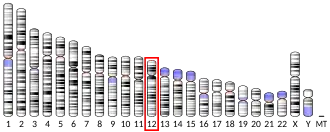

DNA damage-inducible transcript 3

DNA damage-inducible transcript 3, also known as C/EBP homologous protein (CHOP), is a pro-apoptotic transcription factor that is encoded by the DDIT3 gene.[5][6] It is a member of the CCAAT/enhancer-binding protein (C/EBP) family of DNA-binding transcription factors.[6] The protein functions as a dominant-negative inhibitor by forming heterodimers with other C/EBP members, preventing their DNA binding activity. The protein is implicated in adipogenesis and erythropoiesis and has an important role in the cell's stress response.[6]

Mutations or fusions of CHOP (e.g. with FUS to form FUS-CHOP) can cause Myxoid liposarcoma.[49]